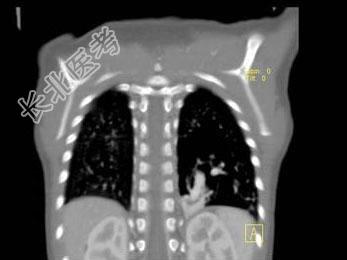

- 单项选择题女,2岁, 咳嗽,结合图像, 最可能的诊断是 ( )

A、先天性肺不张

B、细支气管肺炎

C、先天性支气管闭锁

D、先天性囊性腺瘤样畸形

E、肺隔离症